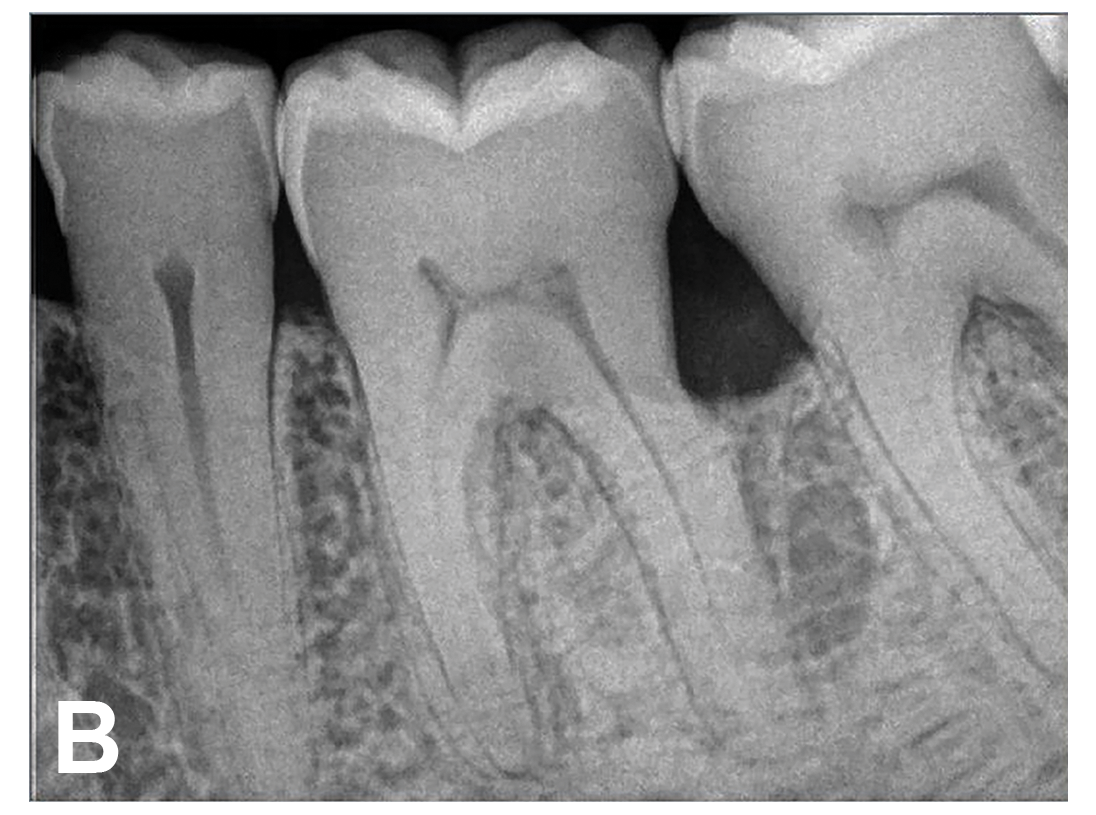

The patient's periodontal disease improved with initial nonsurgical periodontal therapy that involved scaling and root planing. This initial treatment was followed by only SPT every 3 months. Despite treatment, residual deep periodontal probing depths remained, so a decision was made to maximize improvements with nonsurgical therapy and to reassess as needed to determine whether surgical intervention was appropriate. After almost 5 years of SPT and good patient compliance with plaque control and supportive care, the periodontium was stable. Because of the resulting bone formation and improvements in clinical attachment levels (Figure 7 through Figure 13), it was determined that periodontal surgical intervention was not necessary.

In the case report presented, treatment with nonsurgical therapy for 5 years effectively halted destruction and led to bone regeneration and improved clinical attachment levels. Although the primary etiology of periodontal disease is well documented, secondary etiologic and contributing factors are numerous.16 After initial therapy in the current case, there was radiographic evidence of a hypercementosis-like lesion on the distal root of tooth No. 19 (Figure 7 through Figure 10). Hypercementosis is a nidus for plaque accumulation leading to disease progression; however, the presence of this lesion did not explain the disease severity observed for tooth No. 18. Chronic periodontitis is the most widespread form of periodontal disease, and nonsurgical periodontal therapy is the most common type of therapy.17 Scaling and root planning is the gold standard for periodontal treatment. When performed meticulously, they result in improvement of clinical parameters through changes related to tissue shrinkage, long junctional epithelium, new attachment, and in rare circumstances, regeneration.18 The use of nonsurgical periodontal therapy for treatment of periodontal disease requires that the timing for re-evaluation is customized for each patient. Because individuals heal at different rates, the overall medical condition, nutritional intake, environmental and social risks factors, local factors, and colonization of pathogenic bacteria of patients should be considered.7,8 Some patients cannot afford, or choose not to pursue, surgical periodontal therapy. For these patients, clinicians should delay surgical decisions until periodontal risk factors are addressed and nonsurgical efforts are exhausted.

(12.) Follow-up radiographs taken of teeth Nos. 17, 18, and 19 on September 4, 2020 after almost 5 years post-initial scaling and root planing and alternating supportive periodontal maintenance therapy only.

Figure 12

(13.) Follow-up radiographs taken of teeth Nos. 17, 18, and 19 on September 4, 2020 after almost 5 years post-initial scaling and root planing and alternating supportive periodontal maintenance therapy only.

Figure 13